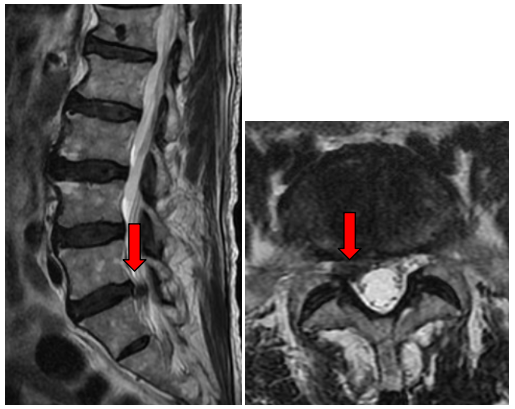

叶爷爷找到佛山市三水区人民医院脊柱关节外科副主任薛厚军主任医师门诊就医。经过详细的问病史、体格检查后,薛厚军主任医师考虑「患者是腰椎疾患引起神经压迫」,进一步完善腰椎磁共振显示「腰 5-骶 1 椎间盘向右侧游离脱出,压迫右侧神经根,合并椎管狭窄」,建议叶爷爷住院治疗。

薛厚军主任医师指出,老年人因腰椎退变严重,很容易出现以腰腿痛、腿麻为主要症状的腰椎管狭窄症,腰椎间盘突出根据突出程度主要分三型:膨出、突出及游离脱出,其中游离脱出的患者症状较重。

一般腰椎间盘突出症的早期以保守治疗为主,老年人腰椎间盘组织多数脱水弹性差,呈黄褐色干枯状,更容易造成机械压迫症状,术中取出的椎间盘组织是典型的高龄椎间盘组织表现,一般保守治疗效果欠佳。